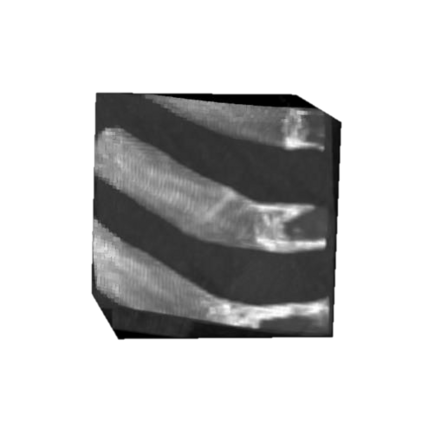

Rib fractures are a common and potentially severe injury that can be challenging and labor-intensive to detect in CT scans. While there have been efforts to address this field, the lack of large-scale annotated datasets and evaluation benchmarks has hindered the development and validation of deep learning algorithms. To address this issue, the RibFrac Challenge was introduced, providing a benchmark dataset of over 5,000 rib fractures from 660 CT scans, with voxel-level instance mask annotations and diagnosis labels for four clinical categories (buckle, nondisplaced, displaced, or segmental). The challenge includes two tracks: a detection (instance segmentation) track evaluated by an FROC-style metric and a classification track evaluated by an F1-style metric. During the MICCAI 2020 challenge period, 243 results were evaluated, and seven teams were invited to participate in the challenge summary. The analysis revealed that several top rib fracture detection solutions achieved performance comparable or even better than human experts. Nevertheless, the current rib fracture classification solutions are hardly clinically applicable, which can be an interesting area in the future. As an active benchmark and research resource, the data and online evaluation of the RibFrac Challenge are available at the challenge website. As an independent contribution, we have also extended our previous internal baseline by incorporating recent advancements in large-scale pretrained networks and point-based rib segmentation techniques. The resulting FracNet+ demonstrates competitive performance in rib fracture detection, which lays a foundation for further research and development in AI-assisted rib fracture detection and diagnosis.